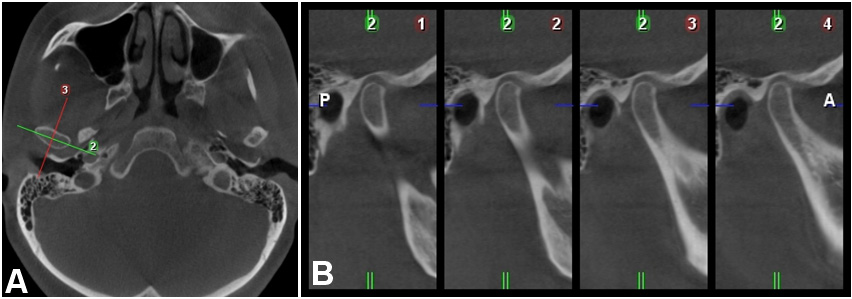

Adjustments to the CBCT images ensured that the vertical reference line ran through the patient’s midsagittal plane in the axial and coronal views. The hard palate was oriented in the sagittal view so that the horizontal reference line was positioned through the anterior and posterior nasal spine. The tool “TMJ module” was activated. When the largest mediolateral width of the condylar process was visible in the axial plane, paracoronal and parasagittal cross-sectional slices were obtained for qualitative and quantitative analysis (Figure 1).